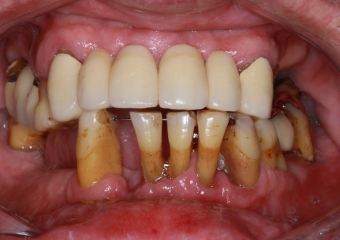

Imagem inicial com vários dentes comprometidos